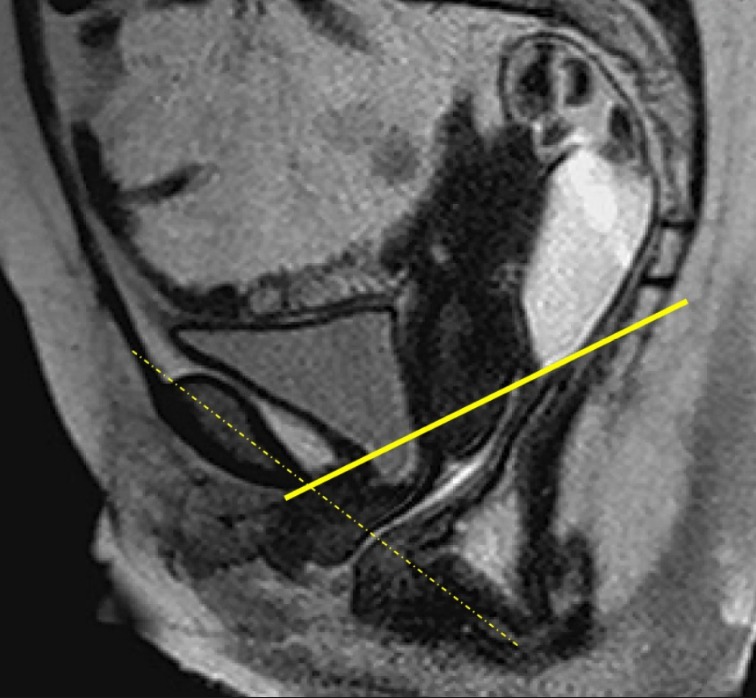

• Abordaje de endometriosis, adenomiosis, miomatosis y afecciones del piso pelviano.